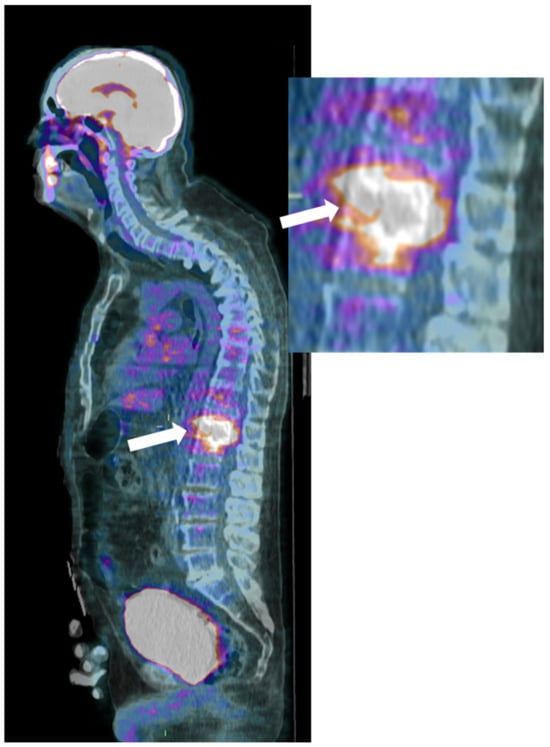

Finally, 18F-Fluorodeoxyglucose-positron emission tomography (18F-FDG-PET) is a sensitive and whole-body imaging tool, though lacking anatomical details; combining it with CT or MRI improves spatial resolution and aids in distinguishing infectious from degenerative abnormalities (Figure 5) [42,45].

It can be interesting to detect multiple intra- and extra-osseous infectious locations with high sensitivity but low specificity, with standardized uptake values (SUV) between 4 and 30 [46]. If required, 18F-FDG-PET/CT can help monitor the treatment efficacy, with a 39% decrease being found in responding patients on 18F-FDG-PET/CT performed at 2 weeks after starting antibiotherapy [44,47]. Additionally, a SUVmax decrease above 15% at 2 weeks would indicate a good treatment response with a sensitivity of 94% and specificity of 67%, i.e., with higher accuracy than concomitant conventional MRI (sensitivity = 37% and specificity = 50%) [44]. However, it must be remembered that there is no routine indication for repeating MRI or 18F-FDG-PET/CT to evaluate the response to treatment.

Figure 5. (FDG) PET-CT, Sagittal reconstruction (magnification on the right) of a 72-year-old male with pyogenic spondylodiscitis of T12-L1 vertebrae. A high pathologic FDG uptake is detected in the disc and vertebral endplates (arrows).